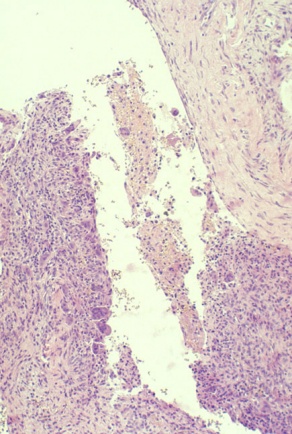

Aneurysmal Bone Cyst